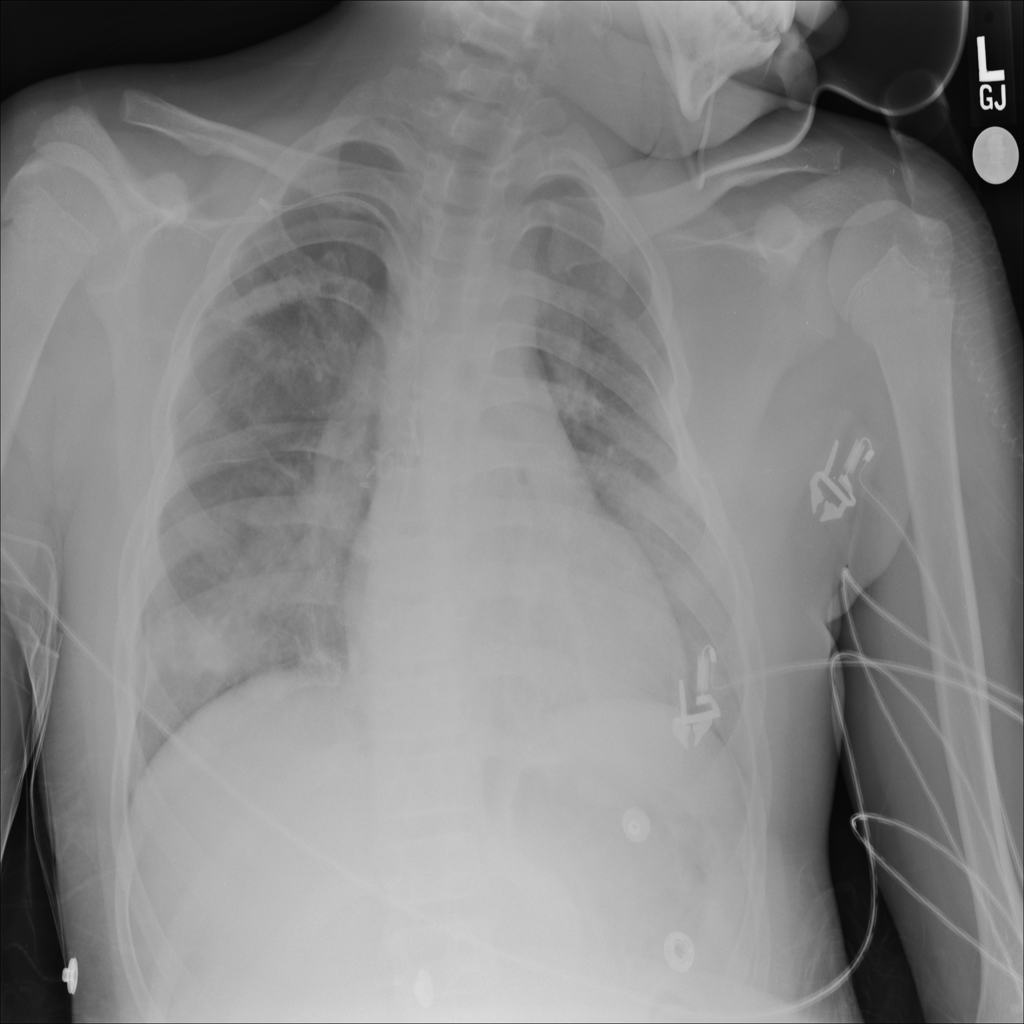

Pneumothorax

Pneumothorax means air is present outside the lung in the pleural space, which can allow part of the lung to collapse. It is an important imaging finding because the size and clinical impact can vary widely.

Showing up to 90 reference images for Pneumothorax.